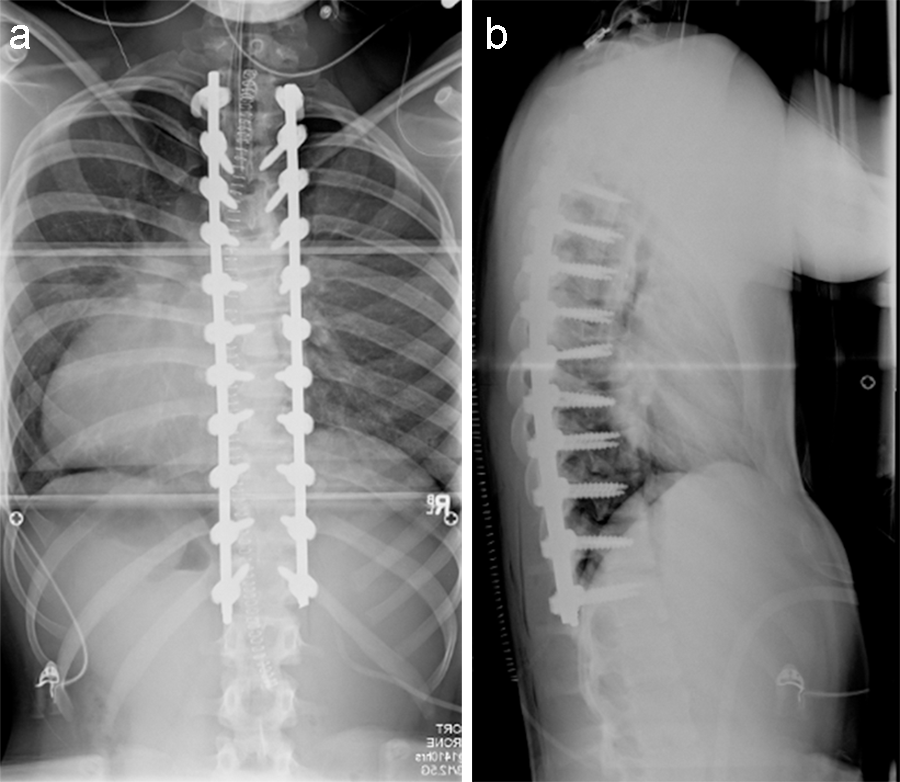

(Case provided by Firoz Miyanji, BC Children's Hospital, Vancouver, BC, Canada)

A 12-year-old girl with AIS underwent T2-T12 posterior spinal instrumentation and fusion.